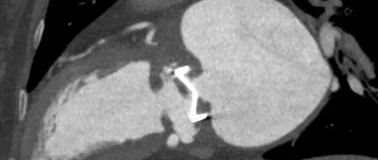

医学影像 yxyx-app 医学影像APP,打造伴随医生快速成长的影像学习社区。与影像园(Xctmr.com)一起提供最全面的影像案例库、基础(解剖、病理、影像诊断)知识、影像技术及考题等,为医生提供最佳的医学影像参考。【所属科室】心内科【基本资料】患者,女,60岁【主诉】持续高热伴寒颤一年【现病史】两年前行二尖瓣置换术+三尖瓣成形术,一年前出现持续高热,给予抗生素治疗,症状反复。...